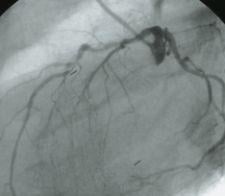

Guerbet’s X-ray contrast agent, Oxilan (ioxilan), is a nonionic low-viscous and low-osmolar monomer.

Significant characteristics of contrast media such as ionicity, chemical structure, osmolality and viscosity have important influences on their efficacy and safety. This emphasis has been implemented in the development of Oxilan, whose chemical characteristics have resulted in high quality imaging with minimal side effects, according to its manufacturer.